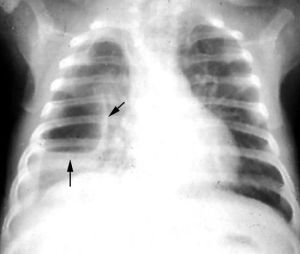

(三)X線檢查

支氣管肺炎的病因不同,因此在X線上所表現的變化既有共同點,又各有其特點。早期見肺紋理增粗,以後出現小斑片狀陰影,以雙肺下野、中內帶及心膈區居多,並可伴有肺不張或肺氣腫,斑片狀陰影亦可融合成大片,甚至波及整個節段。

1.病灶的形態

支氣管肺炎主要是肺泡內有炎性滲出,多沿支氣管蔓延而侵犯小葉、肺段或大葉。X線徵象可表現為非特異性小斑片狀肺實質浸潤陰影,以兩肺、心膈角區及中內帶較多,這種變化常見於2歲以下的嬰幼兒,小斑片病灶可部分融合在一起成為大片狀浸潤影,甚至可類似節段或大葉肺炎的形態。若病變中出現較多的小圓形病灶時,就應考慮可能有多種混合的化膿性感染存在。

2.肺不張和肺氣腫征

由於支氣管內分泌物和肺炎的滲出物阻塞,可產生部分性肺不張或肺氣腫,在小兒肺炎中肺氣腫是早期常見徵象之一,中毒症狀越重肺氣腫就越明顯,在病程中出現泡性肺氣腫及縱隔氣腫的機會也比成人多見。

3.肺間質X線征

嬰兒的肺間質組織發育好,患支氣管肺炎時,可以出現一些肺間質的X線徵象,常見兩肺中內帶紋理增多、模糊。流感病毒肺炎、麻疹病毒肺炎、百日咳桿菌肺炎所引起的肺間質炎性反應都可有這些X線徵象。

4.肺門X線征

肺門周圍局部的淋巴結大多數不腫大或僅呈現肺門陰影增深,甚至肺門周圍濕潤。

5.胸膜的X線征

胸膜改變較少,有時可出現一側或雙側胸膜炎或胸腔積液的現象。儘管各種不同病因的支氣管肺炎在X線表現上有共同點,但又不盡相同,因此,必須掌握好各種肺炎的X線表現,密切結合臨床症狀才能做出正確診斷。